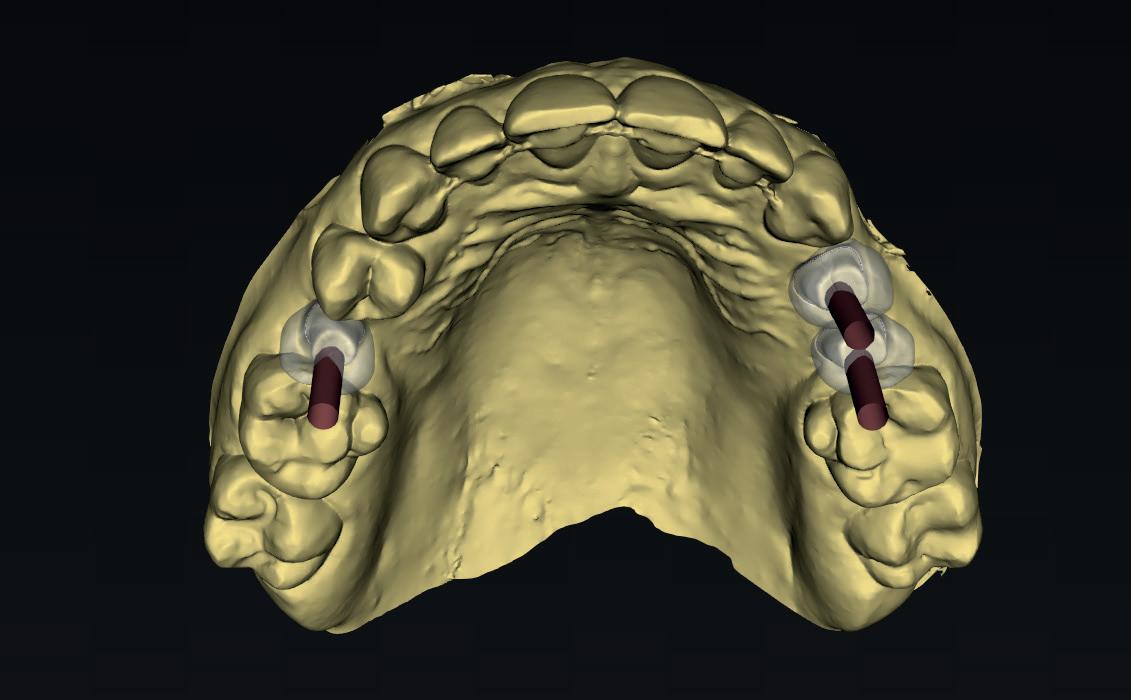

1a. Verlies van buccaal bot na immediaat plaatsing 1b. Jumping Gap 1c-j. Guided geplaatst met een tijdelijke kroon indirect vervaardigd

2a. Keuze om dieper te plaatsen dan nodig door immediaat vervangen

2b. Verkeerde locatie als gevolg van een immediaat plaatsing en onkunde van de behandelaar

2d. Meer palatale preparatie om om te gaan met het te verwachten buccale verlies

2f. Botsubstituut in meest cruciale zone rondom het implantaat